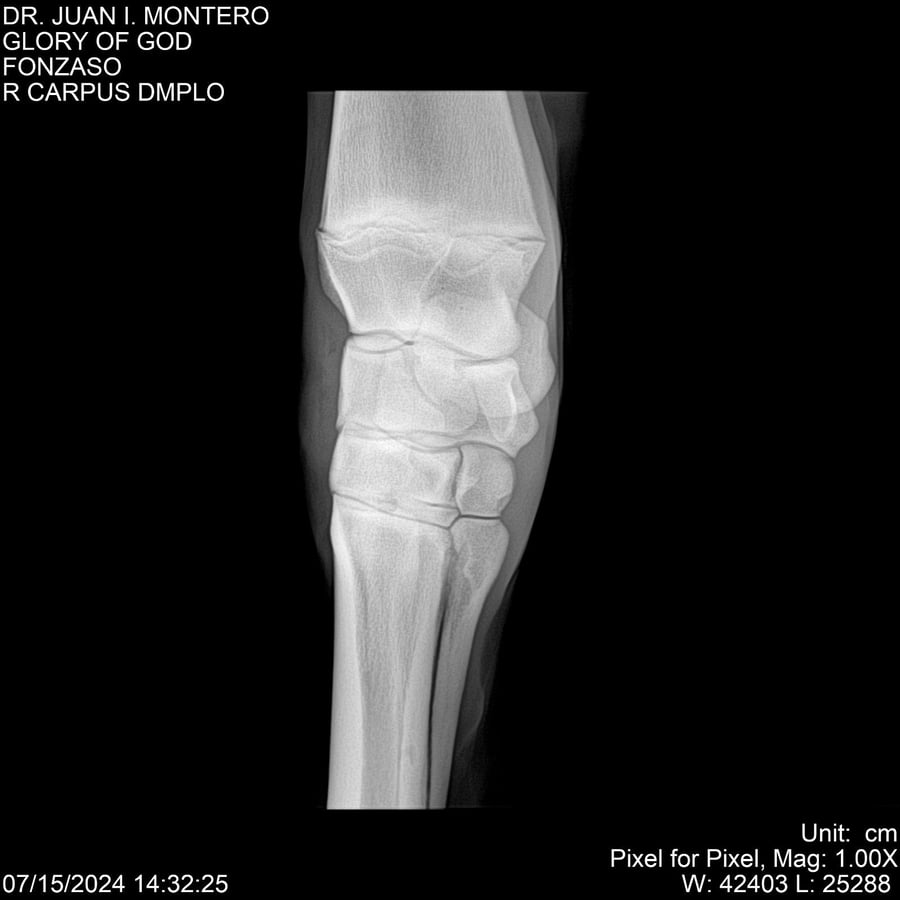

LOTE 10, GLORY OF GOD 🔥 🔥 🔥 Lote Anterior Volver al remate Lote Siguiente Ficha Contacto Montevideo - Ficha del Lote Identificador: #281389 Categoría: Yeguarizos Montevideo - 115 Visualizaciones ClicData Contacto Empresa: Abelenda N. R., Walter Hugo Nombre*: Teléfono* : E-mail* : Mensaje Enviar Registrese gratis Este contenido Exclusivo está disponible sólo para usuarios registrados Ingresar